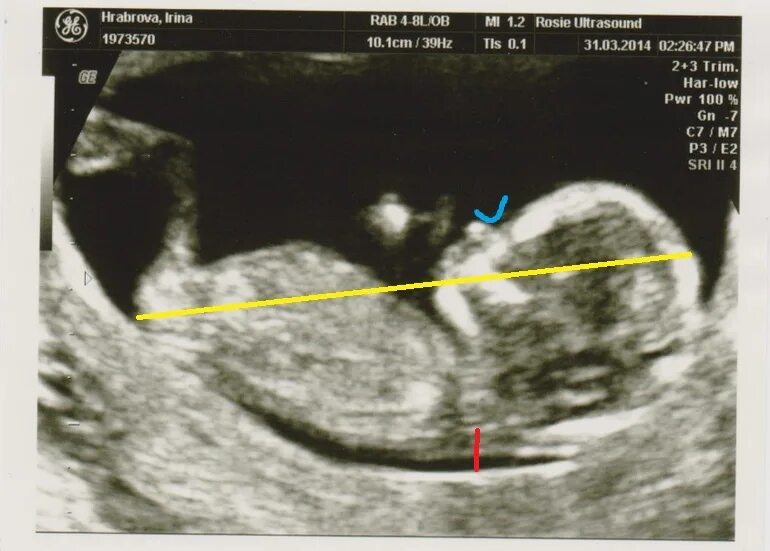

Малыш на первом скрининге